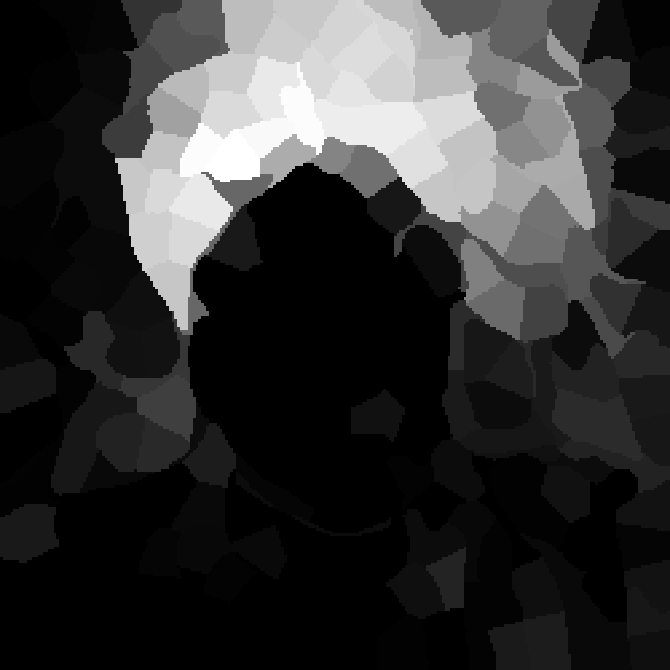

V-C Non-Registered MRI Segmentation Experiments

To demonstrate the robustness of the superpatch structure and the proposed framework, we apply SPM to brain tumor segmentation on multi-modal non-registered Magnetic Resonance Images (MRI). Classical patch-based and multi-atlas structure segmentation methods are based on registered subjects. Consequently, they cannot be efficiently applied in this non-registered context, due to the substantial variation in tumor shape and locations. Superpixels enable to better capture the tumor geometry, thus increasing the segmentation accuracy. Superpixel and supervoxel-based approaches have been applied to tumor segmentation [54]. However, in this work, the neighborhood is not considered and the ANN search is exhaustive, and computed on a large multi-modal histogram descriptor, leading to prohibitive computational time.

SPM can be efficiently applied to tumor segmentation since it quickly finds good correspondences without image registration, and uses the superpixel neighborhood to improve the matching. In this application, the segmentation is computed from a superpixel decomposition [1], then each region (tumor or background) is labeled with SPM.

We present results obtained on the MICCAI multi-modal Brain Tumor Segmentation (BRATS) dataset [49]. This challenging dataset contains real and simulated patient data, with overall poor resolution and large variation of tumor shape and position. For both types, high grade (HG) and low grade (LG) tumors are provided with four modalities: T1, contrast enhanced T1 (T1C), T2, and FLAIR. Overall, there are 20 and 10 real patient data with respectively HG and LG tumors, and 25 images for both HG and LG simulated tumor data. We use the same SPM parameters as in Section V-B, taking a multi-modal histogram, containing the levels of gray intensity on all MRI modalities as descriptor for superpatch matching, and performing the regularization (8) at the pixel scale to compare with pixel-wise ground truths. Each subject is segmented by the remaining of its type in a leave-one-out procedure.

In Fig. 12, we show several tumor segmentation results for all data types.

In Table II, we compare results obtained using different descriptor structures:

patch-based [48], superpixel-based [54],

and superpatch-based (= pixels).

We use the Dice coefficient [55] as evaluation metric,

measuring the overlap between the automatically segmented structure and the ground truth.

The superpixel-based approach

appears very limited since it fails at capturing the tumor context and their location in other images.

Regular patches are also limited in this context, due to the variations in the structure shapes.

Superpatches provide a robust descriptor, since they follow image intensities and capture the superpixel neighborhood,

leading to more accurate segmentation.

These experiments demonstrate that superpatches within the SPM framework provide fast and accurate segmentation results

even on non-registered multi-modal images with poor resolution.